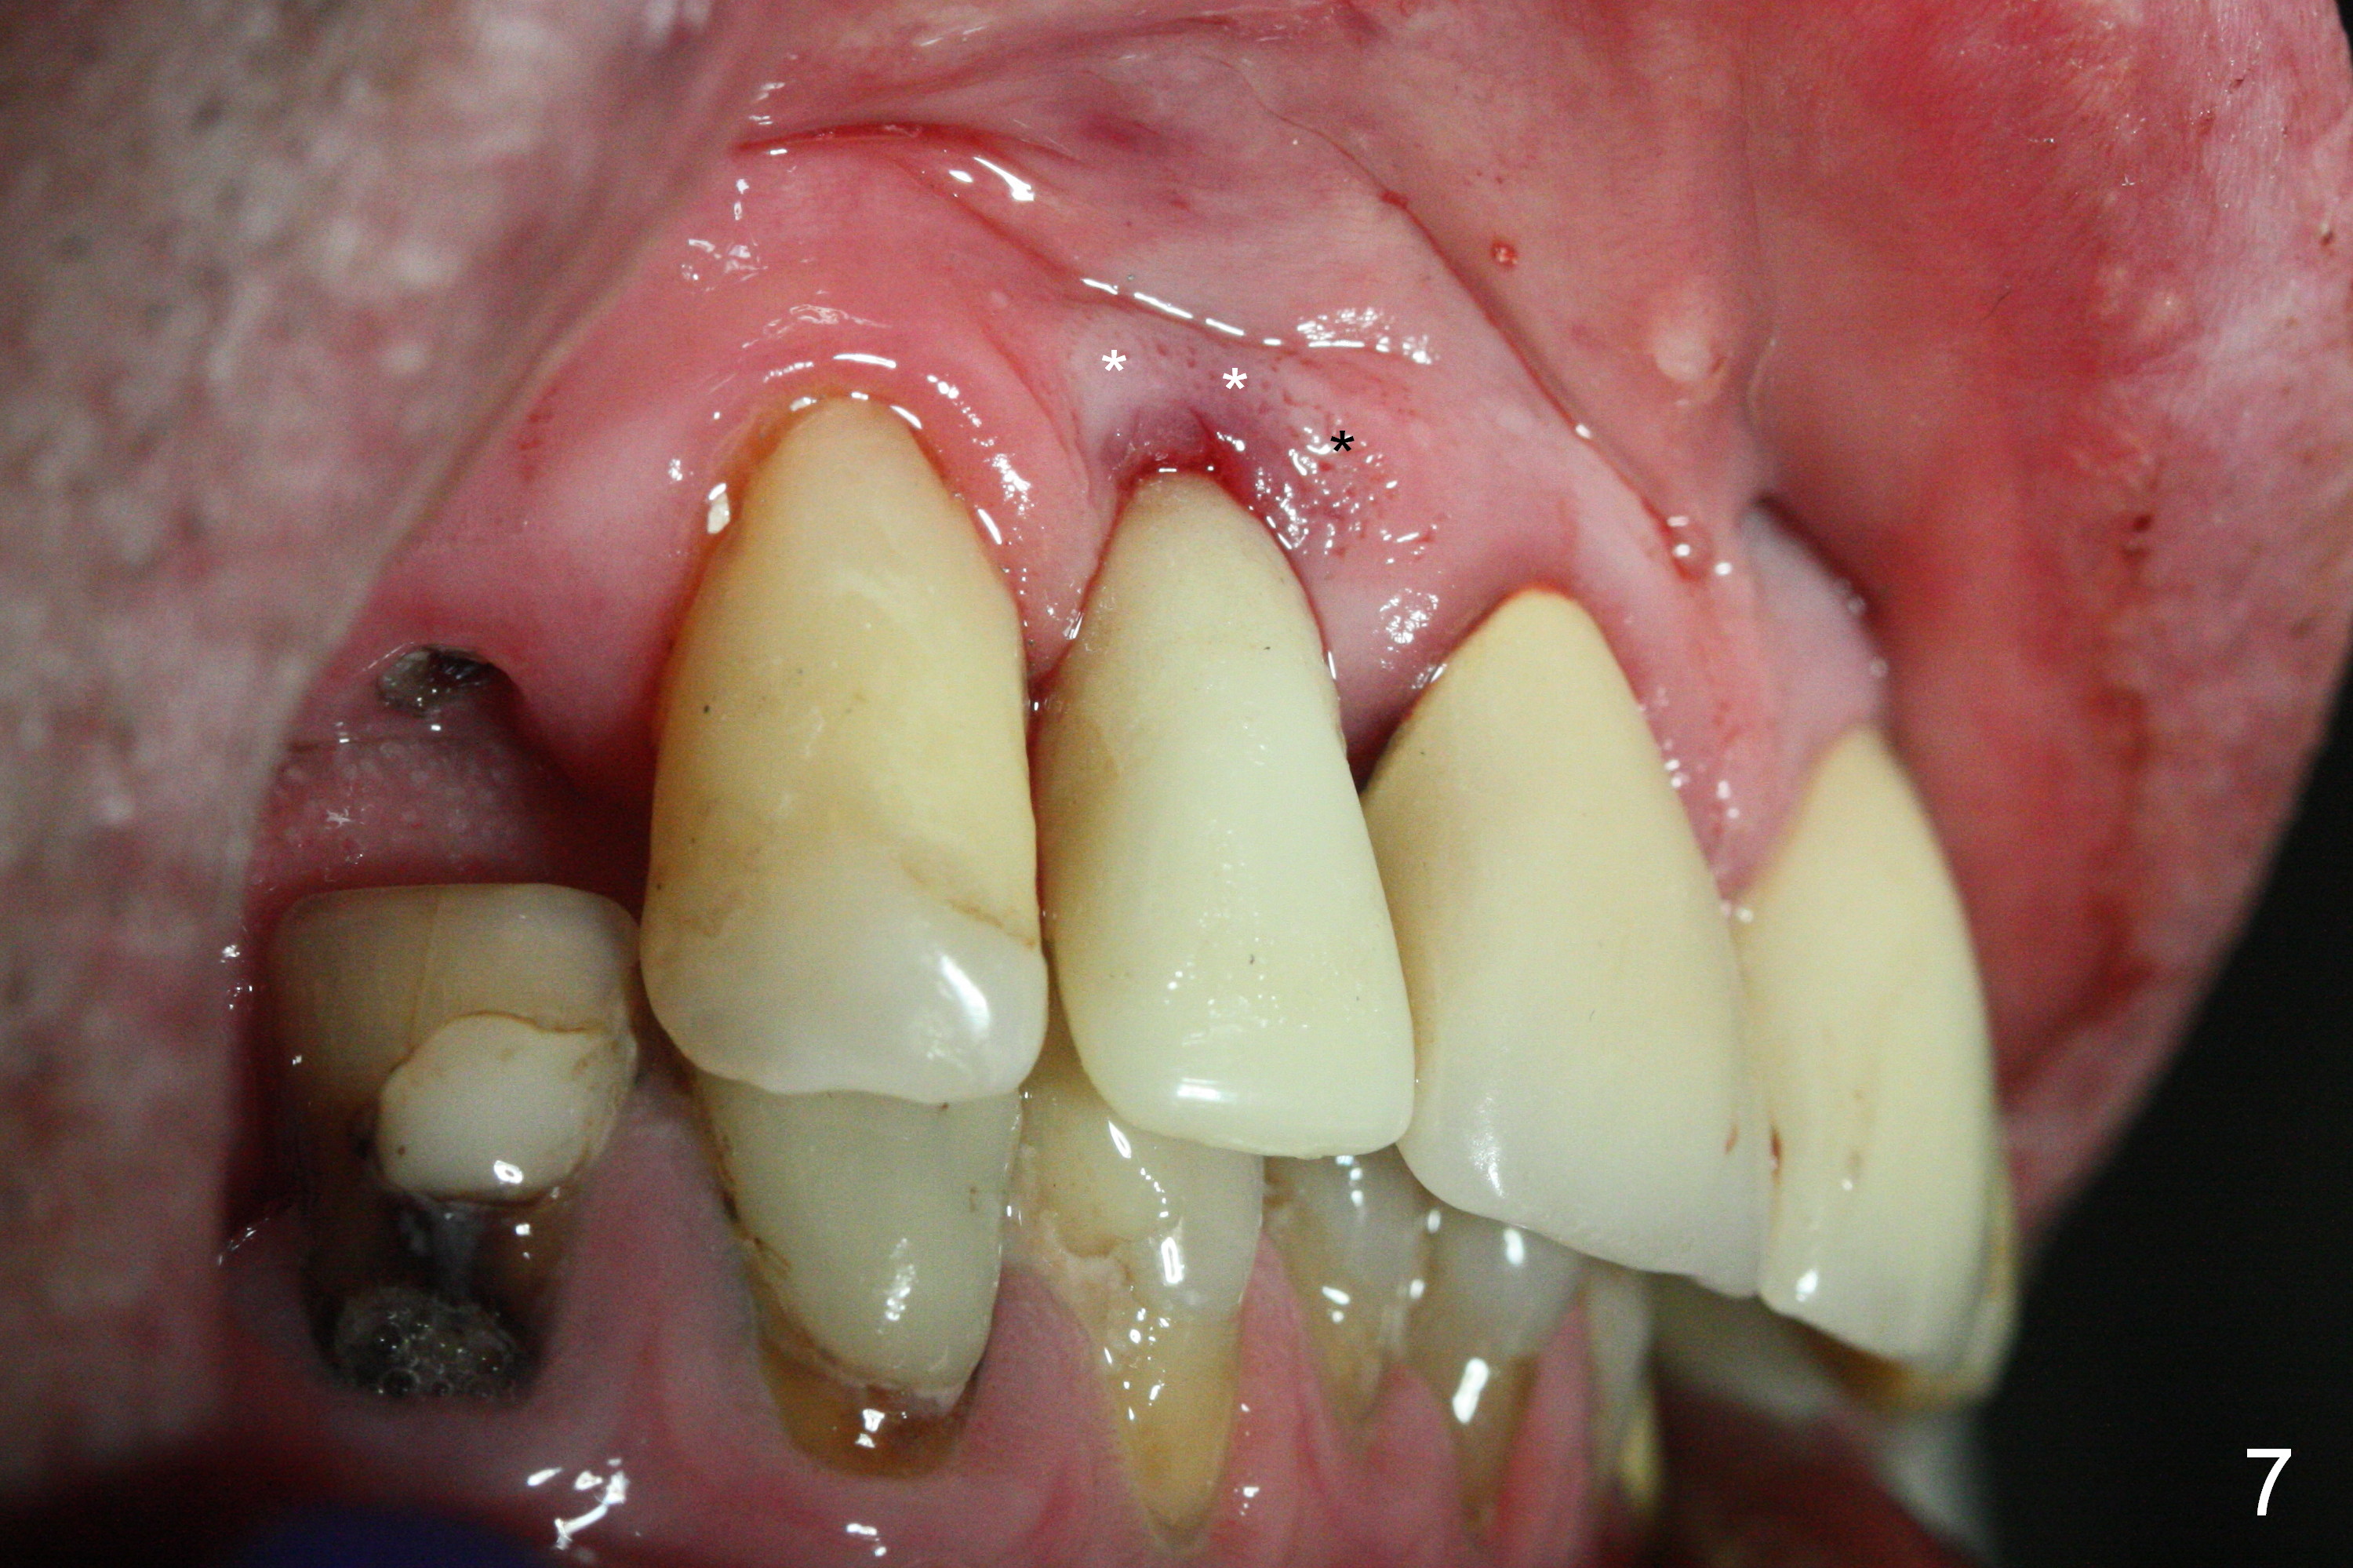

The residual root at #7 is fairly well exposed with buccal gingival recession (Fig.1). The implant placement is flapless (Fig.2-7). What is not shown is that the 3.8x13 mm implant is buccally subcrestally placed (Fig.3). After 1st round of bone graft buccal to the implant, a 4.5x5(5) mm abutment is immediately placed and prepared (Fig.4,5). An immediate provisional is placed after 2nd round of bone graft subgingivally buccally (Fig.6,7). Note the bulging gingiva (*), as compared to that in Fig.4,5. The long implant is chosen because of anterior deep bite (Fig.4) and lack of posterior support (Fig.7).

The gingiva adapts well to the provisional 1 week postop (Fig.8). The buccal gingiva remains recessive and the buccal plate is concave 5.5 months postop (Fig.9-11). It appears that the coronal portion of the buccal plate is resorbed 12 months postop (6 months post cementation, Fig.12 >). Socket shield or smaller diameter implant should have been done to avoid bone loss. Reanalysis of CBCT reveals that implantation apparently increases the bone width and that the buccal plate resorption is not so severe (Fig.13,14 (>: coronal end of the buccal plate)). Panoramic X-ray is taken 2 year 5 month post cementation.